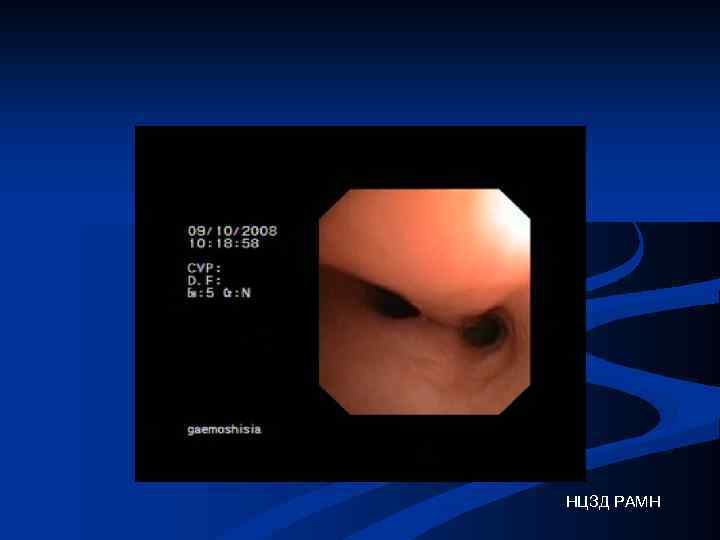

Обострение хронического бронхита НЦЗД РАМН